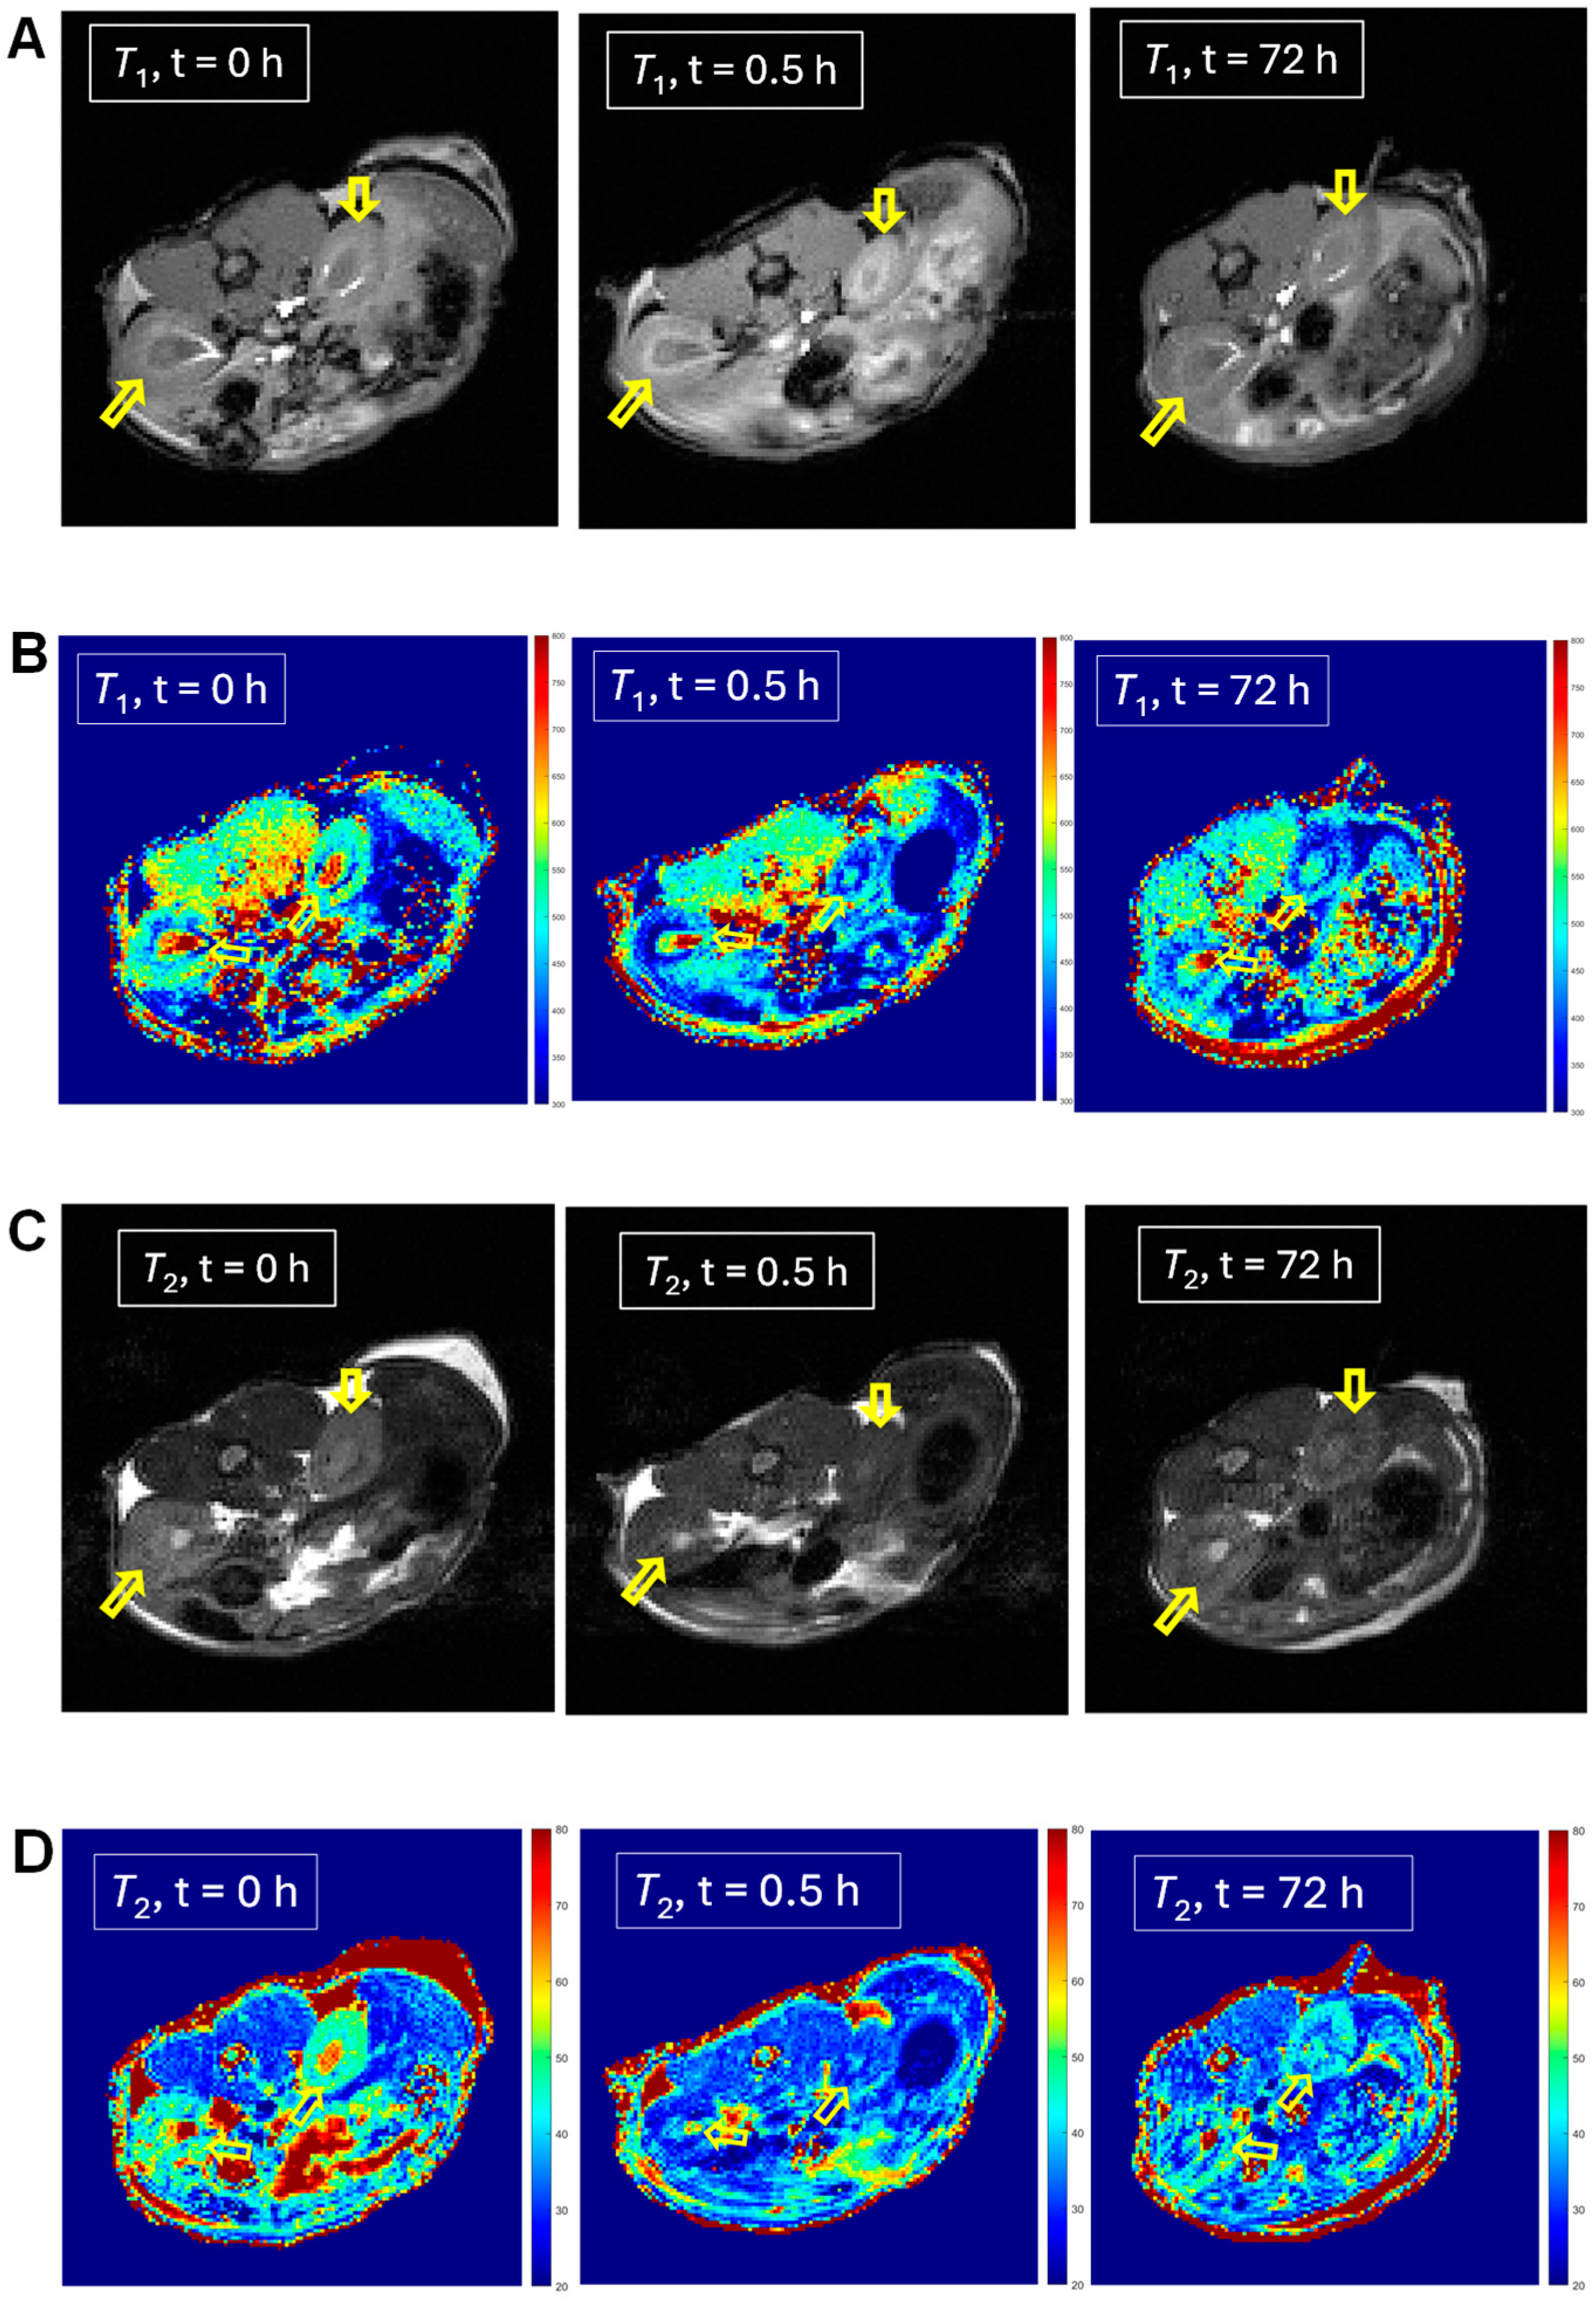

2.3. In Vivo MRI of 1 and 2

| Kidneys | n = 1 | −17 ± 2 | −16 ± 2 | n = 1 | −21 ± 2 | −17 ± 1 |

| Kidneys | n = 9 | +2 ± 5 | −6.5 ± 1.6 | n = 2 | −8 ± 13 | −7 ± 10 |

| Kidneys | n = 7 | −3.4 ± 4.2 | −7.4 ± 1.9 | |||

| Kidneys | n = 4 | −10.5 ± 3.7 | −10.2 ± 2.4 | |||

| Liver | n = 1 | −41 ± 3 | −7.5 ± 2.6 | n = 1 | −1 ± 4 | 0 ± 3 |

| Liver | n = 7 | −6 ± 8 | +6 ± 4 | n = 2 | +9 ± 10 | +7 ± 7 |

| Liver | n = 4 | −19.7 ± 8.5 | −2.9 ± 1.7 | |||

| Liver | n = 3 | −26.0 ± 8.1 | −3.8 ± 2.1 | |||

| Heart | n = 1 | −26 ± 7 | −28 ± 5 | n = 1 | ||

| Heart | n = 5 | +7 ± 10 | −8 ± 7 | n = 2 | ||

| Heart | n = 3 | 0 ± 15 | −19 ± 5 | |||

| Brain | n = 1 | −16 ± 1 | −4.0 ± 1.1 | n = 1 | +8 ± 1 | −1.3 ± 0.8 |

| Brain | n = 2 | −11.9 ± 4.5 | −1.7 ± 2.2 | n = 2 | +10 ± 2 | −0.5 ± 0.9 |